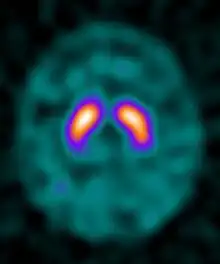

Ioflupane (123I) is the international nonproprietary name (INN) of a cocaine analogue which is a neuro-imaging radiopharmaceutical drug, used in nuclear medicine for the diagnosis of Parkinson's disease and the differential diagnosis of Parkinson's disease over other disorders presenting similar symptoms. During the DaT scan procedure it is injected into a patient and viewed with a gamma camera in order to acquire SPECT images of the brain with particular respect to the striatum, a subcortical region of the basal ganglia.[6] The drug is sold under the brand name Datscan and is manufactured by GE Healthcare, formerly Amersham plc.

Ioflupane has a high binding affinity for presynaptic dopamine transporters (DAT) in the brains of mammals, in particular the striatal region of the brain. A feature of Parkinson's disease is a marked reduction in dopaminergic neurons in the striatal region. By introducing an agent that binds to the dopamine transporters a quantitative measure and spatial distribution of the transporters can be obtained.